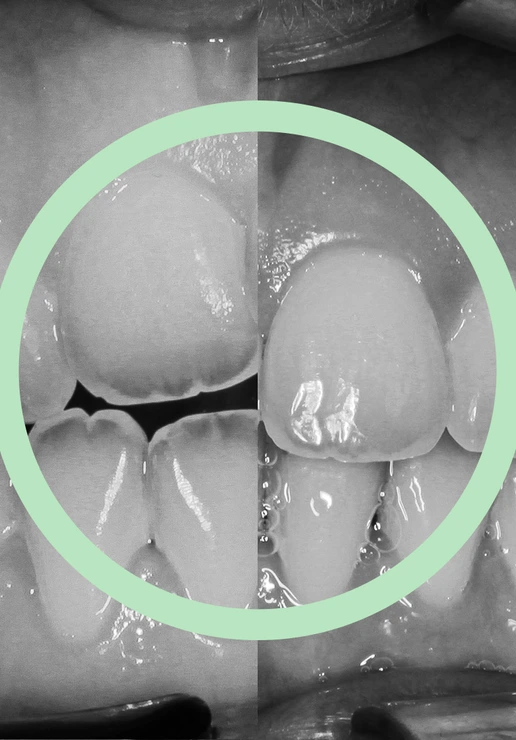

Il morso aperto è un tipo di malocclusione in cui almeno un dente superiore e il corrispondente inferiore non entrano in contatto durante la chiusura della bocca. La forma più comune è il morso aperto anteriore, caratterizzato da una beanza (uno spazio vuoto) tra i denti frontali quando si chiude la bocca.

Morso aperto anteriore